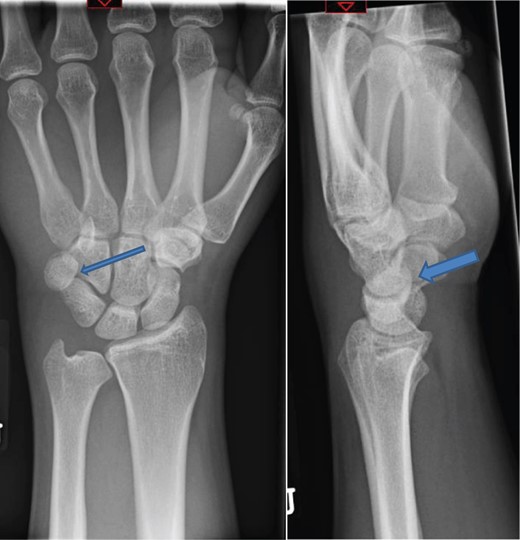

The patient was taken to theatre the following day where a closed reduction of the dislocated pisiform was attempted, however it was unsuccessful. Therefore we then proceed to an open reduction. This was performed through a volar approach through the flexor carpi ulnaris tendon where the piso-hamate joint was exposed and a capsular release performed. This allowed the pisiform to reduce back in to the anatomical position Fig 3. The wrist was immobilized in a neutral position. The patient was followed up in the clinic in two weeks, six weeks, three and six months. The check X-ray performed at the end of six months demonstrated the pisiform remain well reduced, Fig 4. He subsequently regained full a range of motion within the wrist and was further discharged from the clinic.

Image intensifier pictures showing reduction of dislocated pisiform bone.